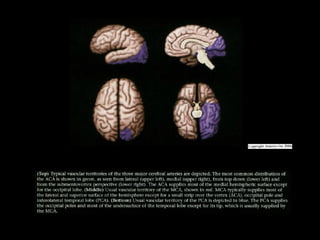

Vascular Territory

• Vascular distribution of ACA, MCA, PCA vary

from individual to individual, have typical as well

as maximum, minimum territories

• Two vascular "watershed" zones exist at

confluence of territorial supply, are vulnerable to

hypoperfusion

- Cortical watershed = subpial confluence of

cortical ACA / MCA / PCA branches

- Deep white matter watershed zone =

confluence of deep cortical penetrating

branches, perforating branches from circle of

Willis (COW)

• Anterior Cerebral Artery

- Perforating branches: Corpus callosum

rostrum, heads of caudate nuclei, anterior

commissure, anteromedial putamen /

globus pallidus / anterior limb internal

capsule (if RAH present)

- Cortical branches: Inferomedial frontal

lobes, anterior 2/3 of medial hemisphere

surface, 1-2 cm over brain convexity

• Middle Cerebral Artery

- Perforating branches: Most of putamen,

globus pallidus, superior half of internal

capsule, most of caudate nucleus, some

deep white matter

- Cortical branches: Most of lateral

surface of cerebral hemispheres, anterior

tip (pole) of temporal lobe

• Posterior Cerebral Artery

- Perforating branches: Much of central

brain base (thalamus, hypothalamus),

midbrain, choroid plexus

- Cortical branches: Most of inferior

surface of temporal lobe, occipital pole,

variable amount of posterolateral surface

of hemisphere

• Basilar Artery

- All of PCA territory (including perforating

branches), most of pons, superior

cerebellum/vermis

• Vertebral Arteries

- Most of medulla, cerebellar tonsils,

inferior vermis / cerebellar hemispheres